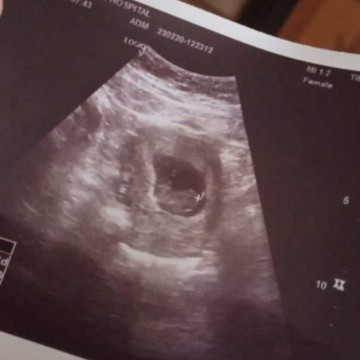

ฝากท้องต้อน7w หมอยังไม่เจอหัวใจ กังวลมาก จิตตกมากเลยคะ จะเจอตอนกี่w คะ เครียดมาก

ตอนนี้จิตตกมากไม่เจอหัวใจน้อง หรือน้องยังเล็กอยู่ เครียดมาก